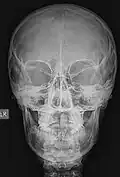

Las imágenes digitales que se adquieren hoy en día, ya sea en radiología digital indirecta (CR) o directa (DR), presentan una gran ventaja debido a la potencialidad que su manejo informático ofrece, en el cual es posible sobre la base de una imagen adquirida aplicar diferentes herramientas como filtros que permiten mejorar el realce de los bordes, suavizar, analizar el histograma y realizar análisis de la calidad de la imagen obtenida. Estas herramientas están disponibles en las consolas de procesado de imágenes de los equipos radiológicos, pero también existen programas dedicados como ImageJ que permiten realizar el análisis de las imágenes, ya sean de uso médico o no. Una de las funcionalidades de ImageJ es la posibilidad de "retocar" la imagen aplicando filtros como los que se observan en las siguientes imágenes en las cuales hemos aplicado a la imagen base de una radiografía de cráneo (al centro) un filtro que permite suavizar la imagen (Imagen 1) y luego a la misma imagen le hemos aplicado un filtro de reforzamiento de los bordes (Imagen 2).